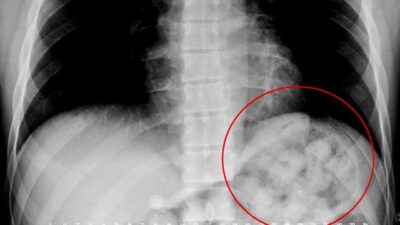

Midesinden 900 gram uyuşturucu madde çıktı